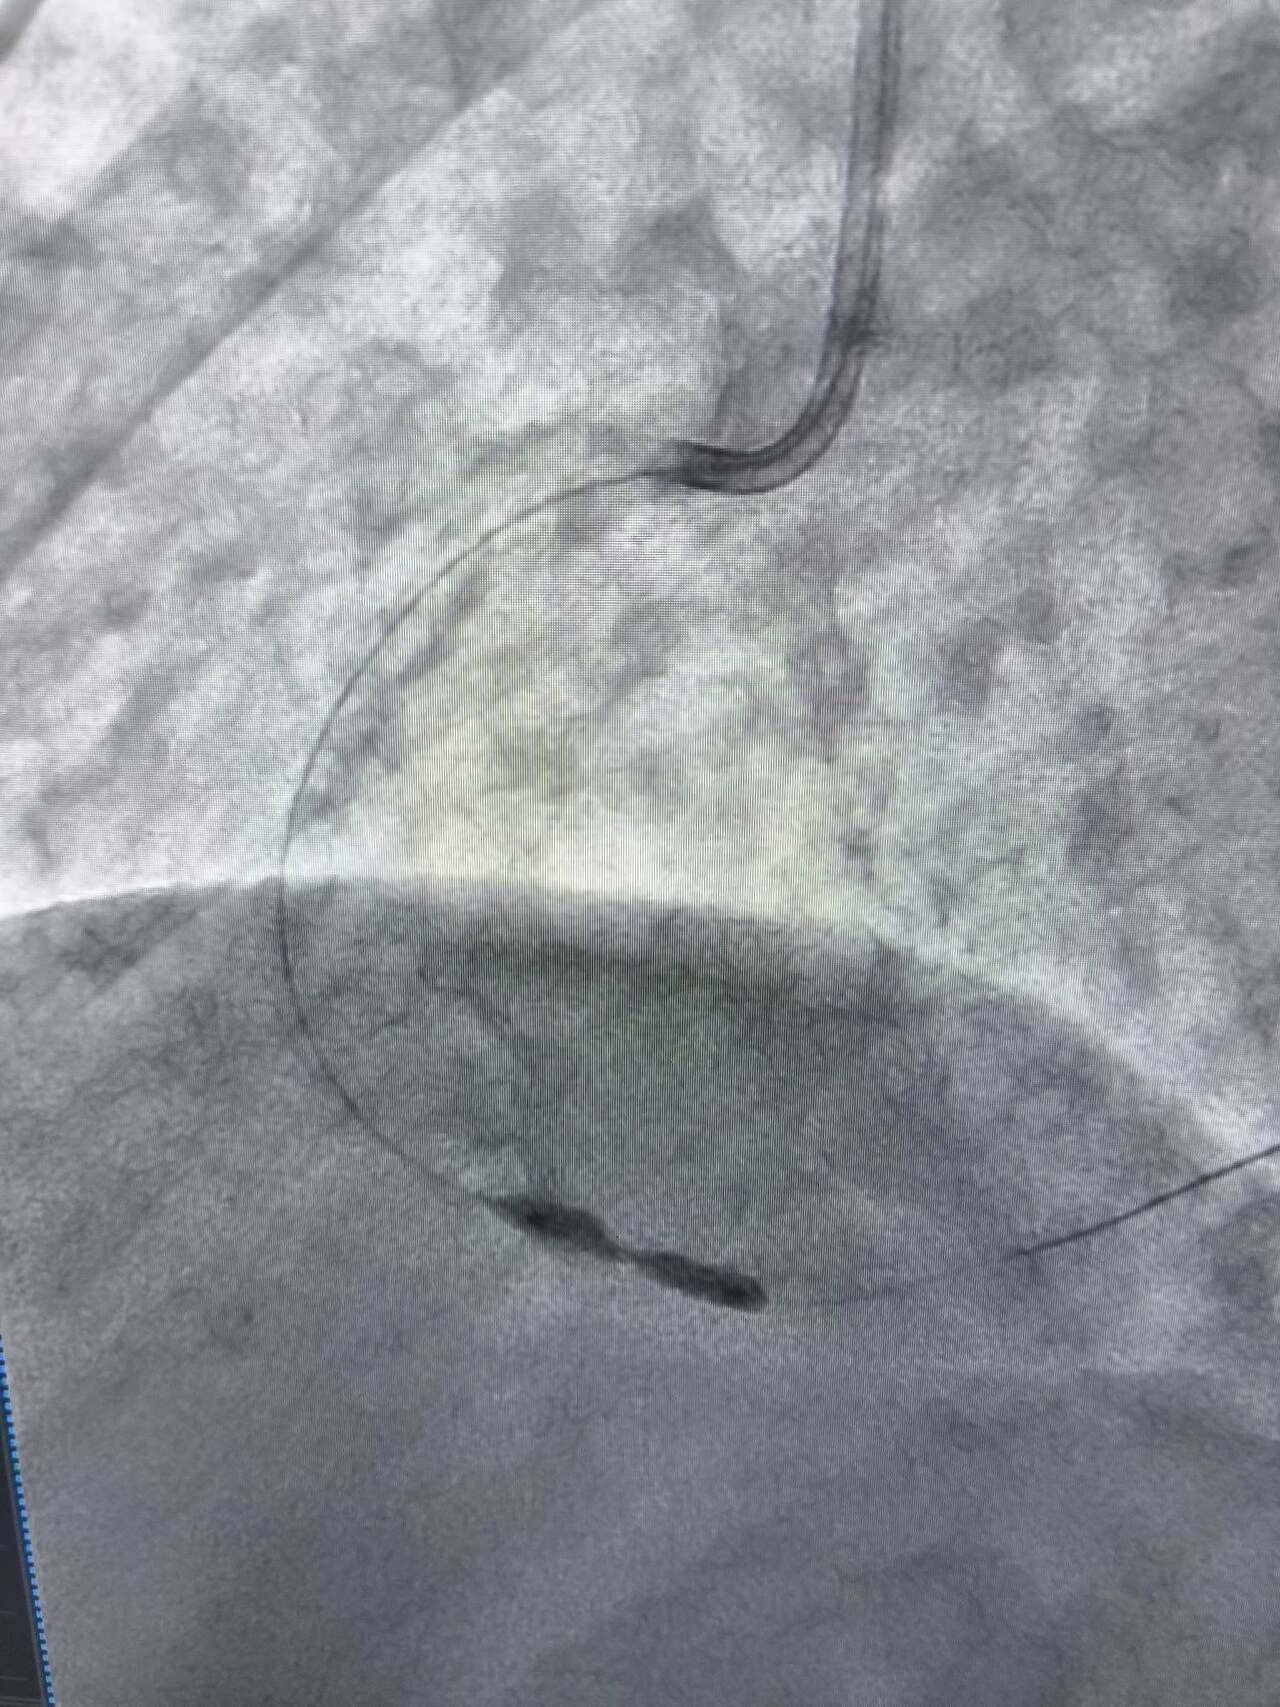

У таких ситуаціях на допомогу приходить ротаблятор – спеціальний пристрій із буром, покритим діамантовим напиленням. Він дозволяє «модифікувати» кальциновану атеросклеротичну бляшку, фактично шліфуючи її та відновлюючи можливість для подальшого стентування судини. Саме таким методом лікарям вдалося ліквідувати перешкоду в артерії та успішно імплантувати стенти.

Це втручання стало важливим кроком для нашої лікарні та всієї області. Ротаційна атеректомія застосовується у найскладніших випадках кальцинованих уражень коронарних артерій, коли стандартна ангіопластика неефективна. Виконання такої процедури означає, що пацієнти Тернопільщини можуть отримати сучасну високоспеціалізовану допомогу без необхідності їхати в інші регіони, – наголосив Богдан Маслій.

Фото Тернопільської обласної клінічної лікарні